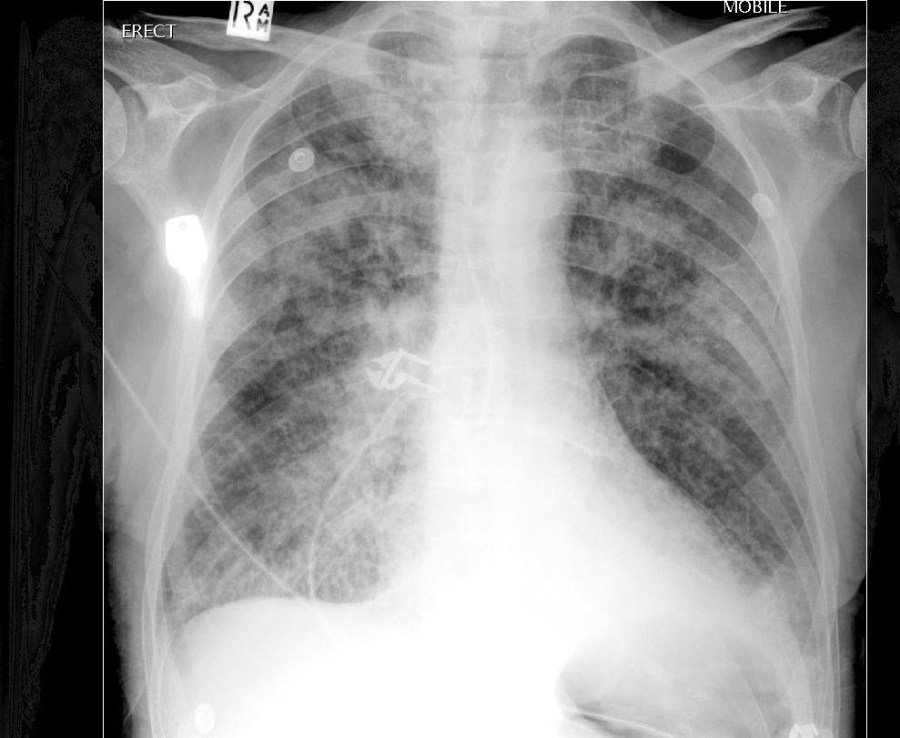

Introduction: As medicine is ever changing, new diseases and symptomatology are being classified differently according to the etiology, presentation, clinical findings, and treatments of subsets of disease pathology. There have been various names throughout the continued advancement of medicine for acute pulmonary edema, but there have also been various clinical findings and differences in treatments …